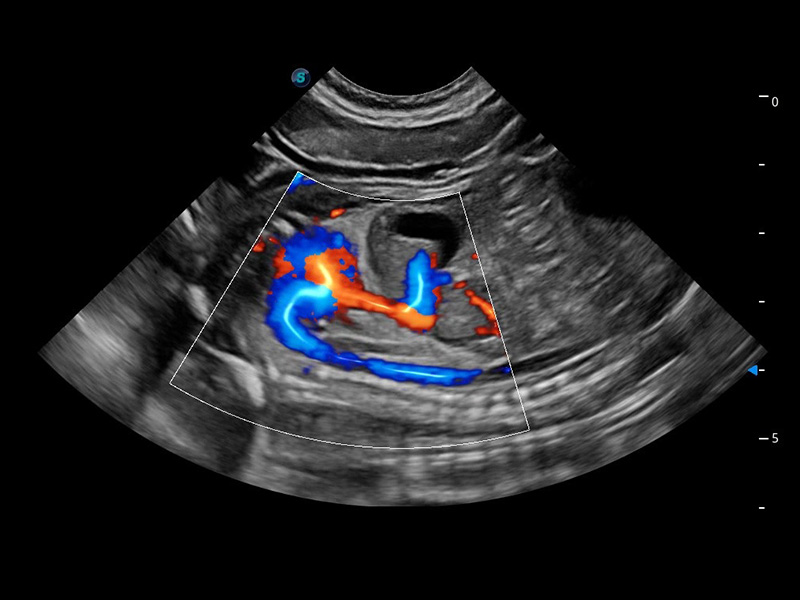

ProPet 60 作为一款高端台式动物超声设备,为动物医生的日常诊断提供了一系列贴合动物临床需求、解决临床实际问题的高级成像功能。凭借全系列高清探头,满足医生对腹部、心脏、生殖、浅表、肌骨等成像的所有需求,切实帮助您提升检查效率,提高诊断信心。

兽用彩色多普勒超声诊断系统

动物是人类最亲密的朋友和最值得信赖的伙伴。MILE米乐集团官网也一直致力于探索动物专用的超声影像解决方案。 全新推出的ProPet系列,是MILE米乐集团官网在动物超声影像智能化、专业化、精准化的一次跨越式革新。动物不能用言语来表述自己的不适,通过超声影像,ProPet系列搭建了动物医生与不同物种沟通的“桥梁”,为动物医生注入了“治愈之力”。